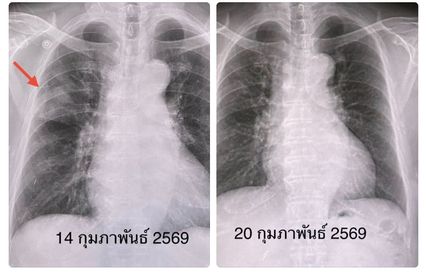

ผลตรวจร่างกาย ไม่มีไข้ ระดับออกซิเจนที่ปลายนิ้ว 96% หัวใจเต้นเร็ว 130 ครั้ง/นาที หัวใจเต้นผิดจังหวะ ฟังปอดปกติ ทำคลื่นไฟฟ้าหัวใจ พบหัวใจห้องบนเต้นระรัว (Atrial fibrillation) ตรวจหัวใจดัวยคลื่นเสียงความถี่สูง (Echocardiogram) ไม่พบความผิดปกติ เจาะเลือด เม็ดเลือดขาวในเลือดปกติ ส่งเลือดเพาะเชื้อ ไม่ขึ้นเชื้อแบคทีเรีย เอกซเรย์ปอด มีฝ้าขาวลักษณะคล้ายก้อนที่ปอดข้างขวากลีบบน แยงจมูกส่งตรวจสารพันธุกรรม RT-PCR พบเชื้อโบคาไวรัส (Bocavirus)

เคสนี้แพทย์วินิจฉัย ว่า โบคาไวรัส (Bocavirus) ทำให้เกิดปอดอักเสบ และภาวะหัวใจห้องบนเต้นระรัว (Arial fibrillation) ในผู้สูงอายุรายนี้ ซึ่งมีโรคประจำตัวเบาหวาน และไขมันสูง หลังให้ยา cordarone หัวใจกลับมาเต้นเป็นปกติ ให้การรักษาตามอาการ ไอลดลง ไม่มีเสมหะ ไม่มีไข้ ติดตามเอกซเรย์ปอดกลับมาปกติในเวลา 6 วัน